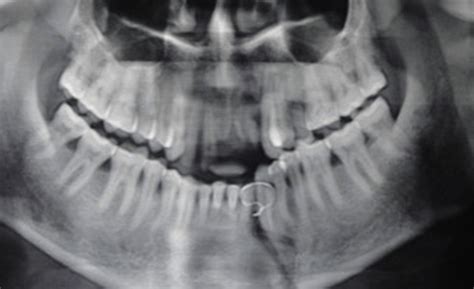

Mandibular Fracture OPG

Mandible Fracture X-ray

Mandibular Fracture Classification Radiology